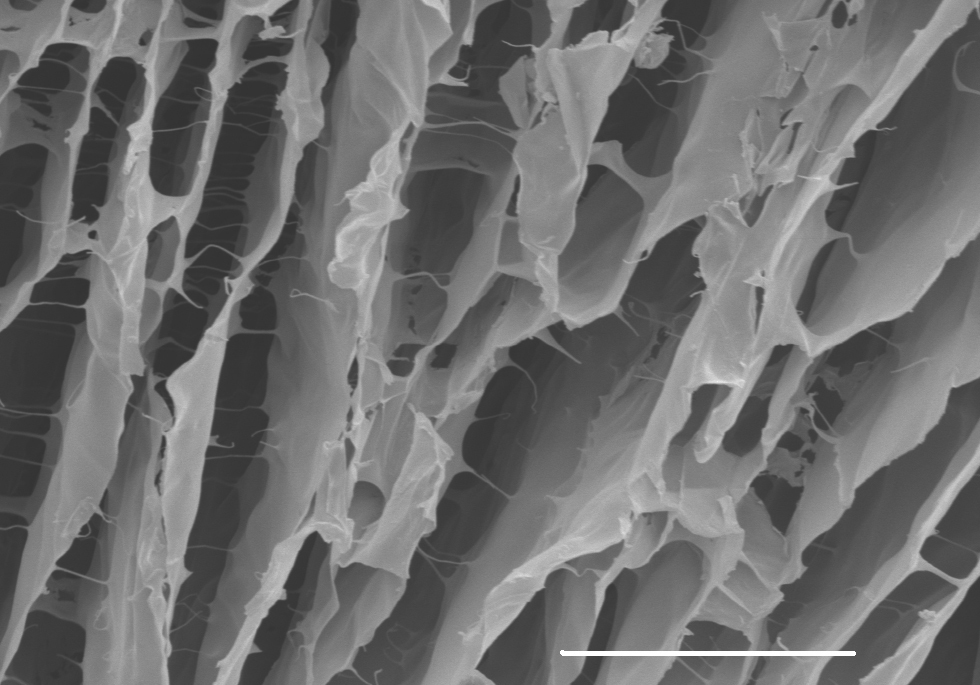

Хорошо зарекомендовали себя нанотехнологии и в процессе заживления и восстановления тканей. Регенерация клеток похожа на реставрацию здания: клетки и биомолекулы на специальных «строительных лесах», скаффолдах (от англ.scaffold - строительные леса), прикрепляются и ведут работы по заживлению тканей.

Российские учёные с помощью нанотехнологий смогли напечатать скаффолды на 3D-принтере. В то же время исследования показали, что эти конструкции достаточно прочные и биосовместимые. То есть, благодаря нанотехнологиям можно не только заживлять ткани, но и даже успешно пересаживать органы.